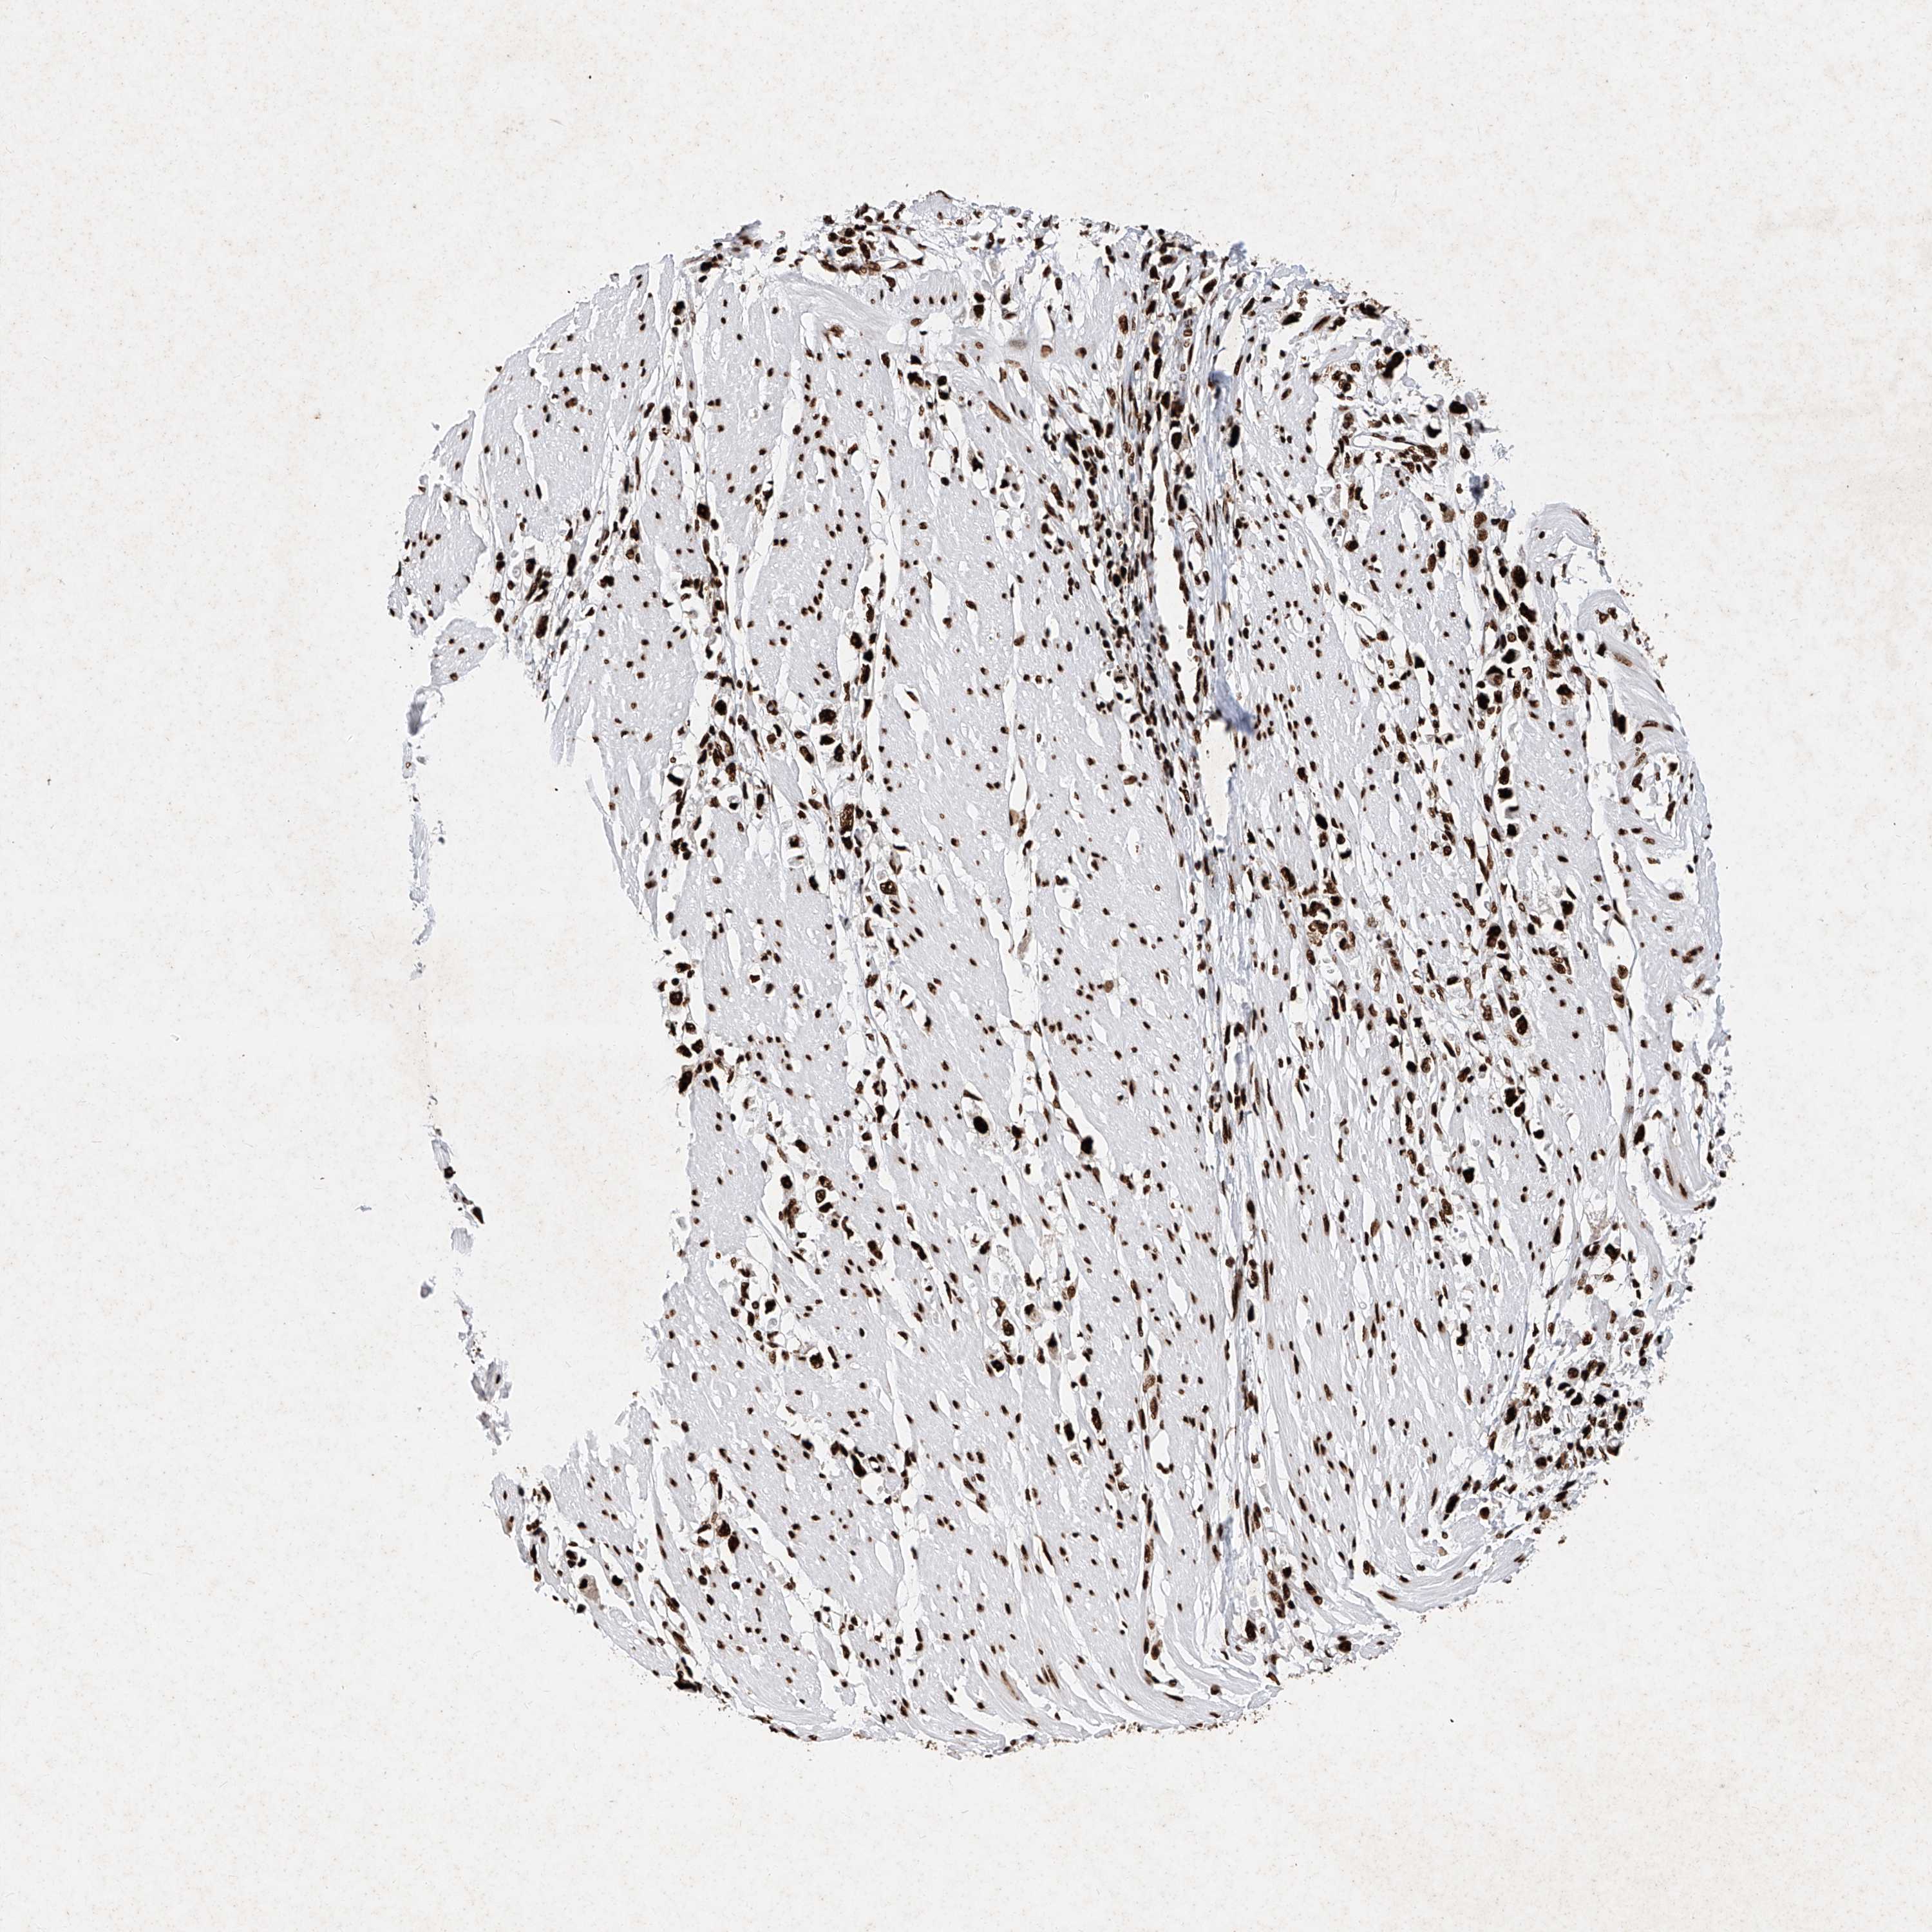

STOMACH CANCER - Protein expressioni

A mouse-over function shows sample information and annotation data. Click on an image to view it in a full screen mode. Samples can be filtered based on level of antibody staining by selecting one or several of the following categories: high, medium, low and not detected. The assay and annotation is described here.

Antibody stainingi

Antibody staining in the annotated cell types in the current human tissue is reported as not detected, low, medium, or high, based on conventional immunohistochemistry profiling in selected tissues. This score is based on the combination of the staining intensity and fraction of stained cells.

Each image is clickable and will lead to virtual microscopy that enables deeper exploration of all samples and also displays staining intensity scores, fraction scores and subcellular localization as well as patient and tissue information for each sample.

Antibody HPA029005

Antibody CAB034889

Staining

High

Medium

Low

Not detected

Intensity

Strong

Moderate

Weak

Negative

Quantity

>75%

75%-25%

<25%

None

Location

Nuclear

Cytoplasmic/membranous

Cytoplasmic/membranous,nuclear

Adenocarcinoma, NOS